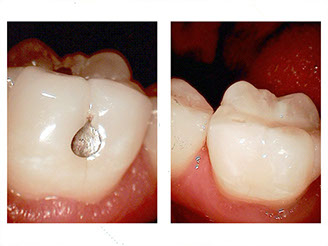

Ceramic crowns

A crown covers the tooth for various reasons:

New ceramic materials provide the strength of a full metal crown, with the appearance of a natural tooth. Watch this video to see how old crowns compare to new materials. If you've ever had a broken crown, talk to Dr. Young about the possibilities of that never happening again.

Dr. Young warrants his ceramic restorations against breakage for 15 years. If your dentist doesn't warranty your crowns, give us a call.